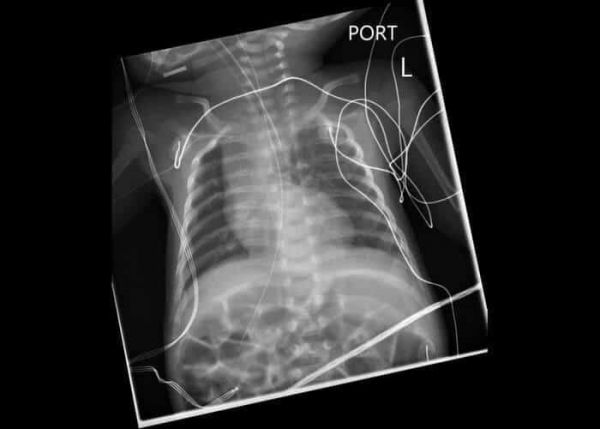

У этого мужчины из Коннектикута диагностирована редкая наследственная патология – экзостозы. Дополнительно к существующим у человека 206 костям у него выросло еще около 92. Значительная их часть локализуется в области грудины и суставов. Врачи смогли удалить 42 с помощью ряда операций, проведенных в 2010 году. Примечательно, что некоторые были соразмерны с пультом от телевизора. Хирургическое лечение имело ряд последствий. Например, еще в юношестве парню повредили нерв, в результате чего начала неметь нога. Редкое заболевание передалось и трем детям Дэна, но у них не был обнаружен доминантный ген, который проявляется приблизительно в половине случаев. Наследственные экзостозы были диагностированы только в 1,6 тыс. семей. Действенного лечения не выработано.